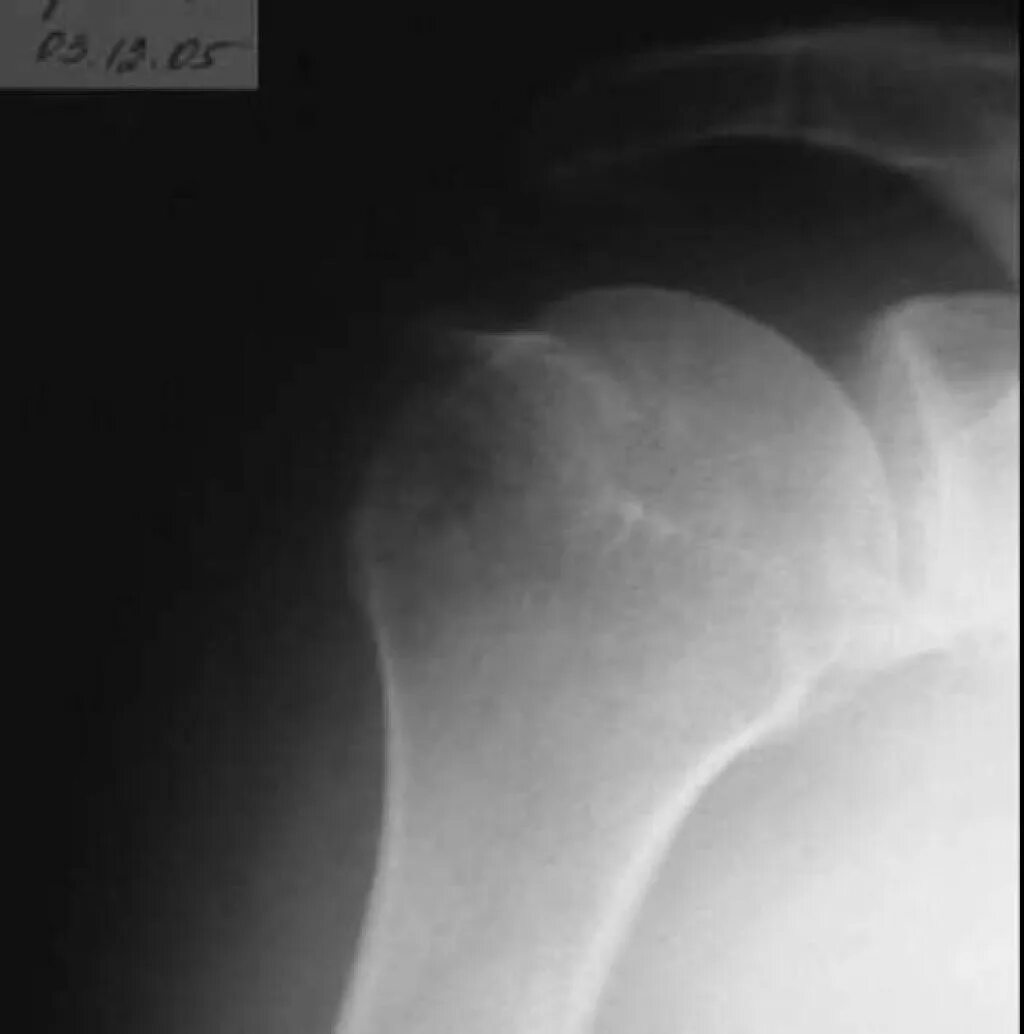

Перелом б бугорка